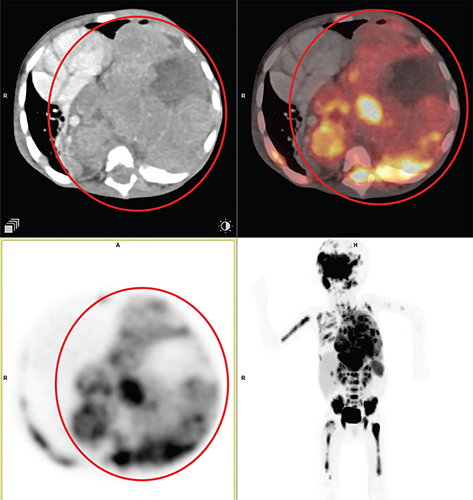

According to histological characteristics, thymomas are divided into five different types: type A thymoma (containing an unusual form), type AB thymoma, type B thymoma (divided into B1, B2, and B3 thymomas), micronodular thymoma with lymphoid stroma, and metaplastic thymoma (22). The presence of FDG uptake in the normal and hyperplastic thymus, especially in younger adults and children, limits the role of 18F-FDG PET/CT in thymoma imaging. Physiological uptake in the thymus has been reported in 28% of patients under 40 years of age and up to 73% in children under 13 years of age (26). Although research has been limited, higher grade tumors tend to have higher FDG activity, 18F-FDG PET/CT has not been shown to reliably distinguish between different grades of thymic tumors (27, 28). An example of typical thymoma is shown in Figure 1.

Fig 1

Figure 1. Type A thymoma. Anterior mediastinal mass that was pathologically confirmed as type A thymoma. FDG PET/CT images include axial CT (top left panel), fused axial PET/CT (top right panel), axial PET (bottom left panel), and maximum intensity projection (MIP) PET image (bottom right panel). In the red circle, there is a soft tissue density mass with well-defined contour showing homogenous enhancement in CT with moderate FDG uptake on PET. No evidence of infiltration of adjacent structures. No other metabolically active disease in the whole-body survey.